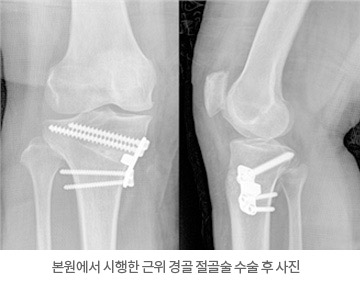

- └ 하지부동